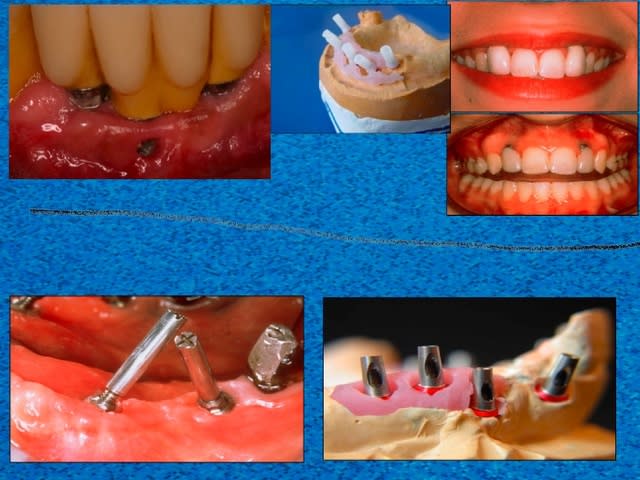

S1 lmklqw - Eugenol

S3 wkklx9 - Eugenol

Pano atbqmf - Eugenol

02/11/2007 à 15h29

photos et radio de mauvaise qualité je n'avais pas mon matériel sous la main ce matin mais uniquement la caméra endobuccale que je ne manie que rarement (ca se voit),depuis un cambriolage je ne laisse plus rien de valeur facilement transportable .Mais j'ai pensé à ton sujet alors j'ai paré au plus pressé

Ce patient( proche de la famille) a été équipé site de 36 37 il y à deux ans et mis en provisoire à l'époque parti à 700 km du cabinet me contacte mardi en me disant qu'il revenait pour la toussaint mais qu'il avait un petit souci du coté droit....

Viens donc ce matin pour me montrer (tant pis pour le pont)

et voilà le résultat : fracture des deux petites provisoires au niveau de l'extension mesiale ; voussure vestibulaire que l'on devine malgré la photo de mauvaise qualité .